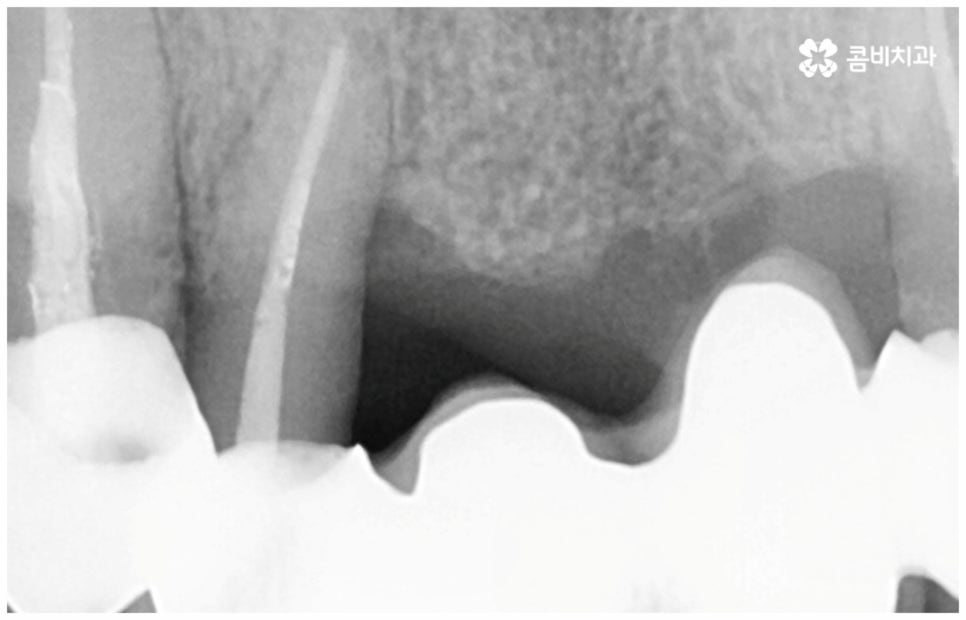

그러나 노화나 구강 질환을 원인으로 한 경우에는 식립 절차가 좀 더 복잡해 질 수 있는데요. 잇몸병을 예로 들어 생각해 보면 자연스러운 노화 및 관리 소홀로 인해 치아 주변 조직 (잇몸, 치주인대, 치조골 등) 에 염증 반응이 생기는 병인 치주 질환이 많이 심해졌을 때 상황에 따라 해당 자연 치아를 살리지 못하고 발치를 해야할 수도 있는 거예요. 이렇게 치주질환을 이유로 임플란트 식립을 진행할 때에는 식립 성공률을 높이고 임플란트수명 을 늘리기 위해 먼저 치주질환 치료를 선행해 줘야 하며, 환자분들의 상황에 따라 뼈이식 또는 상악동 거상술을 통해 잇몸뼈를 보충해 줘야 할 수도 있어요. 치조골이 이미 많이 녹아 있거나 병증이 극심하다면 임플란트 식립 난이도가 매우 높아지거나 때로는 불가능해 질 수 있기 때문에 다양한 임상 경험을 통해 풍부한 노하우를 가지고 있는 의료진에게 진단 및 치료를 받는 것이 굉장히 중요한 포인트라고 할 수 있습니다.

임플란트 치아에는 치아가 받는 충격을 분산시켜 주고 세균 및 외부 이물질이 침투하는 것을 막아주는 역할을 하는 치주 인대가 없기 때문에 위생 관리가 제대로 이뤄지지 않는다면 자칫 임플란트를 지지하는 잇몸에 세균이 증식하여 염증이 생기기 쉬우므로 정기 검진을 통해 임플란트 상태를 지속적으로 관찰하면서 매일의 올바른 칫솔질과 주기적인 스케일링 치료를 통해 구강 내부를 늘 청결하게 관리해 줄 필요가 있어요. 임플란트 치아 자체에는 충치가 생기지 않지만 임플란트 표면에는 치태와 치석이 쌓이기 쉬우며 여기에 증식한 세균이 주변 잇몸 내로 침투해 염증을 유발하게 되면 잇몸이 빨갛게 붓거나 피가 나고 구취가 유발될 수 있어서 주의하셔야 할 거예요. 이러한 임플란트 주위염이 심해지면 잇몸뼈까지 녹아내려 임플란트를 제거하고 재수술을 받아야 하는 경우가 생기기도 하니 철저한 사후 관리 시스템을 갖춘 치과에서 케어받으시길 권유드리고 있습니다.